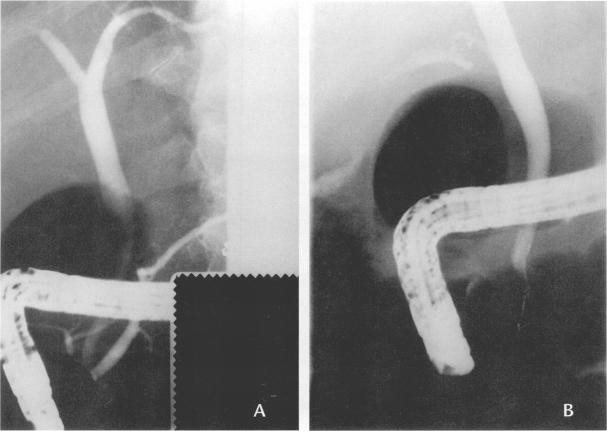

Glibenclamide-induced cholestasis.

West J Med. 1998 Apr;168(4):274-7.